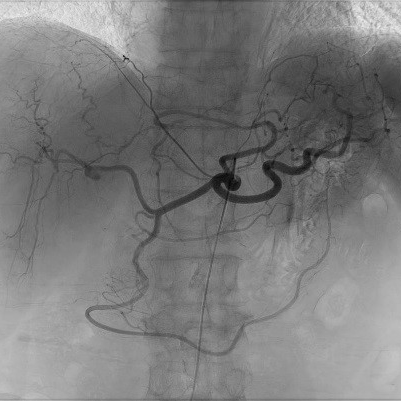

脳血管撮影

脳血管撮影では、頭頸部の血管をカテーテルから造影剤を流して撮影します。血管の走行を観察したり、必要に応じて血管の狭窄や閉塞を広げる治療や、動脈瘤をコイルで塞栓する治療、脳腫瘍などへの栄養血管に対して手術前の塞栓術を行ったりします。脳の血管をみる検査にはCTやMRIなどといった撮影もありますが、血管撮影装置での脳血管撮影ではそれらよりも細かい血管の状態まで観察することができます。

右内頚動脈瘤

右総頚動脈造影